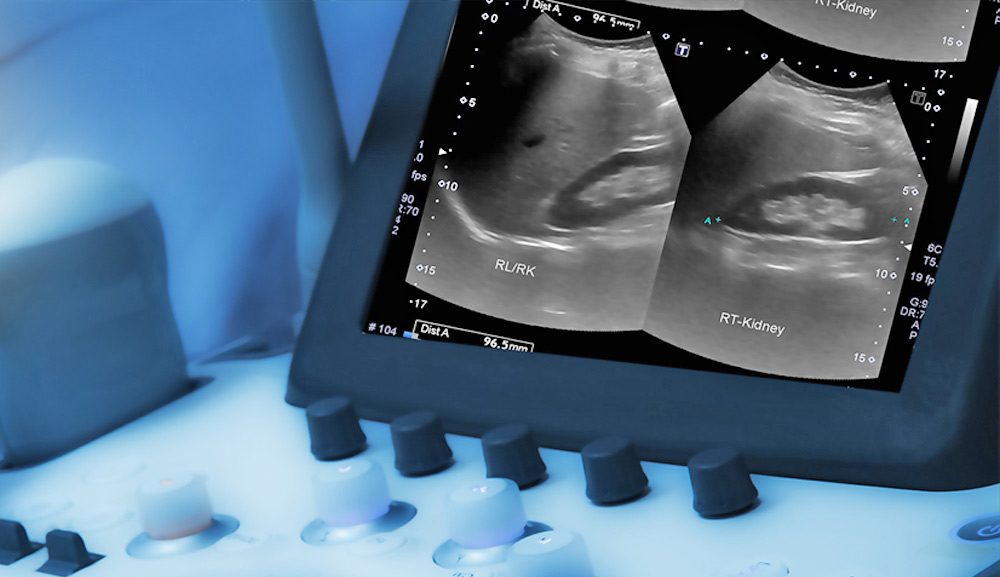

The case of Adriana Smith has sparked an ethically significant debate by confronting public opinion with an extreme situation: a 30-year-old African American woman, a nurse by profession and mother of a seven-year-old child, was diagnosed with brain death on February 19, 2025, at Emory Midtown University Hospital, located in Atlanta, Georgia. Adriana was in the ninth week of her second pregnancy when she experienced a severe headache. She went to the hospital but was discharged without undergoing diagnostic imaging studies. Hours later, her health deteriorated rapidly, and she was readmitted with brain clots that led to the diagnosis of brain death. Since then, she has been maintained on life support for more than ninety days to allow the fetus to reach extrauterine viability.

During clinical follow-up, doctors detected an excessive amount of fluid around the fetus’s brain, a possible sign of hydrocephalus, which could compromise its neurological development. The family, in addition to facing the pain of Adriana’s situation, has expressed distress over the uncertain prognosis of the baby, who could be born with some disability or might not survive after birth. These concerns, combined with the emotional and economic effort required to maintain prolonged treatment, have further complicated the ethical and human conflict surrounding this case.